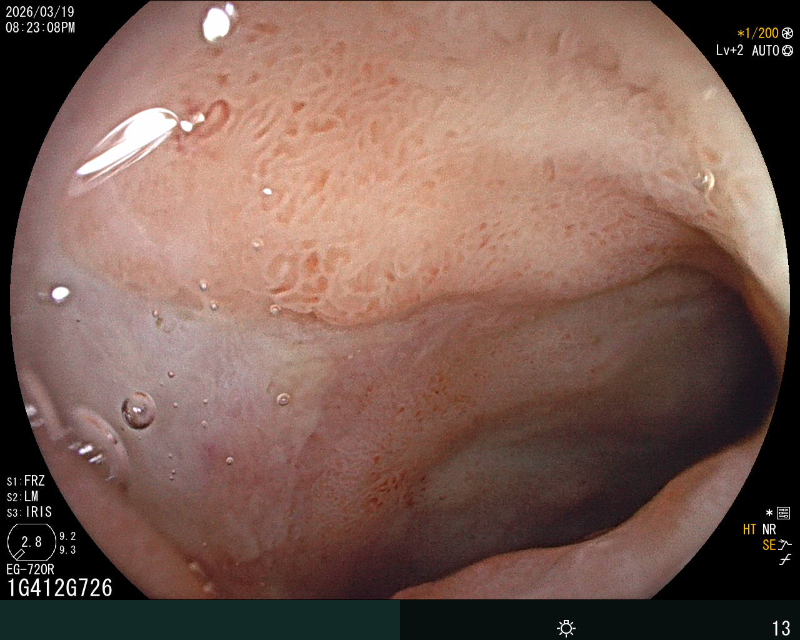

十二指肠球部治疗后

治疗后十二指肠降段

在重症医学科(ICU)团队严密监护保障下,消化科内镜团队克服患者休克、体位受限等困难,紧急开展床旁急诊胃镜。镜下可见出血病灶位于十二指肠球部出现糜烂渗血,一处8×4mm 深溃疡覆血痂及污苔,活动性渗血明显,且黏膜严重水肿、肠腔狭窄,内镜镜身不能通过,操作难度极大。内镜团队通过精准操作,利用去甲肾上腺素联合冰盐水反复冲洗创面,收缩血管减少出血,再通过内镜通道将止血粉均匀喷洒于糜烂及溃疡面。药物覆盖后,渗血即刻停止,创面形成稳定保护层,成功止血。次日胃镜复查显示,患者溃疡创面已覆盖厚白苔,活动性渗血完全消失,黏膜水肿显著消退,肠腔狭窄改善,止血效果确切,为后续抗感染、纠正休克等综合治疗赢得关键时间。目前患者生命体征平稳,未再出现消化道出血。